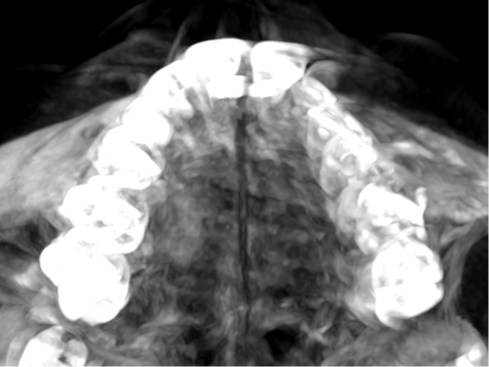

Indications for expansion with braces, RDP or aligners.

Expansion patterns with aligners in Children: case reports

Biomechanics of Dental expansion with aligners: everything you need to know

The only event where you will see real cases treated with the Invisalign Palatal Expander